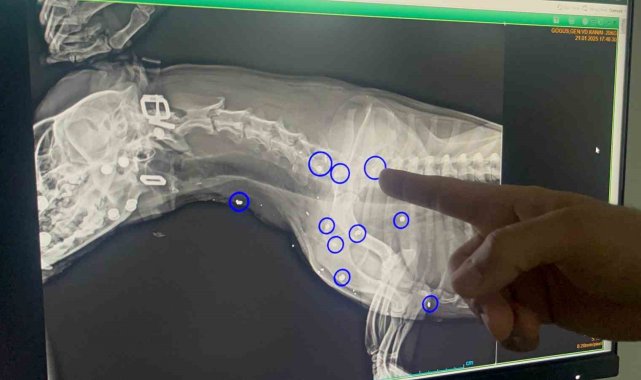

Eskişehir'de kimliği belirsiz kişi veya kişilerce tüfekle vurulan ve 12 yerinden yara alan sokak köpeği, hayvan severler tarafından tedavi ettirildi.Tepebaşı ilçesi Aşağısöğütönü Mahallesi'nde sahipsiz köpek, hayvan severlerin iddiasına göre 21 Ocak tarihinde av tüfeği benzeri bir silah ile vuruldu. Vücudunun 12 yerine saçma değen ve yaralanan köpek özel bir veteriner kliniğinde tedavi alındı.Köpeğin sahiplendirileceğini söyleyen Yaren Ünlü şöyle konuştu;"İlk geldiğinde zaten saat 05.00 civarlarında geldi. Karnının tok olduğunu düşündüğümüz için anestezi uygulayamadık. Ertesi gün röntgeni çekildiğinde de 12 yerinde saçma yaraları olduğunu gördük. Hayati organlara çok yakın olduğu için saçmaları ne yazık ki alamadık. Şu anki süreçte de kalbinde bir büyüme olduğu için ne yazık ki anestezi uygulayamıyoruz, sonraki süreçte kurşun yaralarından dolayı zehirlenme var mı diye durumu mutlaka değerlendirip test ve kontrollerini yapacağız".

Eskişehir'de vurulan 12 yerinden yaralanan köpek hayvan severler tarafından tedavi ettirildi

Eskişehir'de kimliği belirsiz kişi veya kişilerce tüfekle vurulan ve 12 yerinden yara alan sokak köpeği, hayvan severler tarafından tedavi ettirildi.